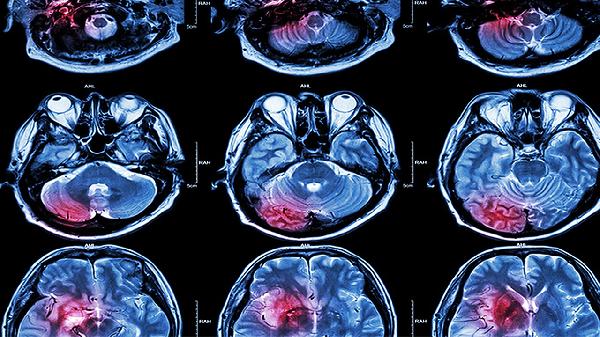

脑血栓溶栓治疗需严格遵医嘱使用药物,常用溶栓药物主要有注射用阿替普酶、注射用尿激酶、注射用瑞替普酶、注射用重组人TNK组织型纤溶酶原激活剂、注射用重组链激酶等。溶栓治疗具有严格的时间窗限制,需在发病后尽早进行。